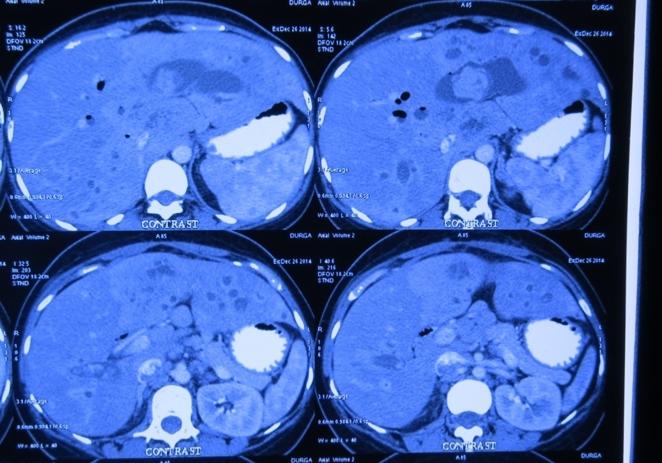

Challenging emergency during the COVID: Child’s A CLD with HUGE gastric varices uncontrolled

Child’s A CLD with HUGE gastric varices uncontrolled by Endoscopic glue and attempted EUS coiling. One salvage option would be TIPSS with balloon vascular occlusion but due to logistics we went for modified sugiura procedure. Splenectomy + Gastro esophageal devascularisation with anterior Gastrotomy and overseeing of gastric varices with pyloroplasty. Images show 1 CECT showing large gastric fundal varices. 2,3,4 Gastro Esophageal devasc 5, 6 Large fundal varices before and after oversewing. 7. Anterior gastrotomy 8. Pyloroplasty. Postoperative recovery was uneventful.